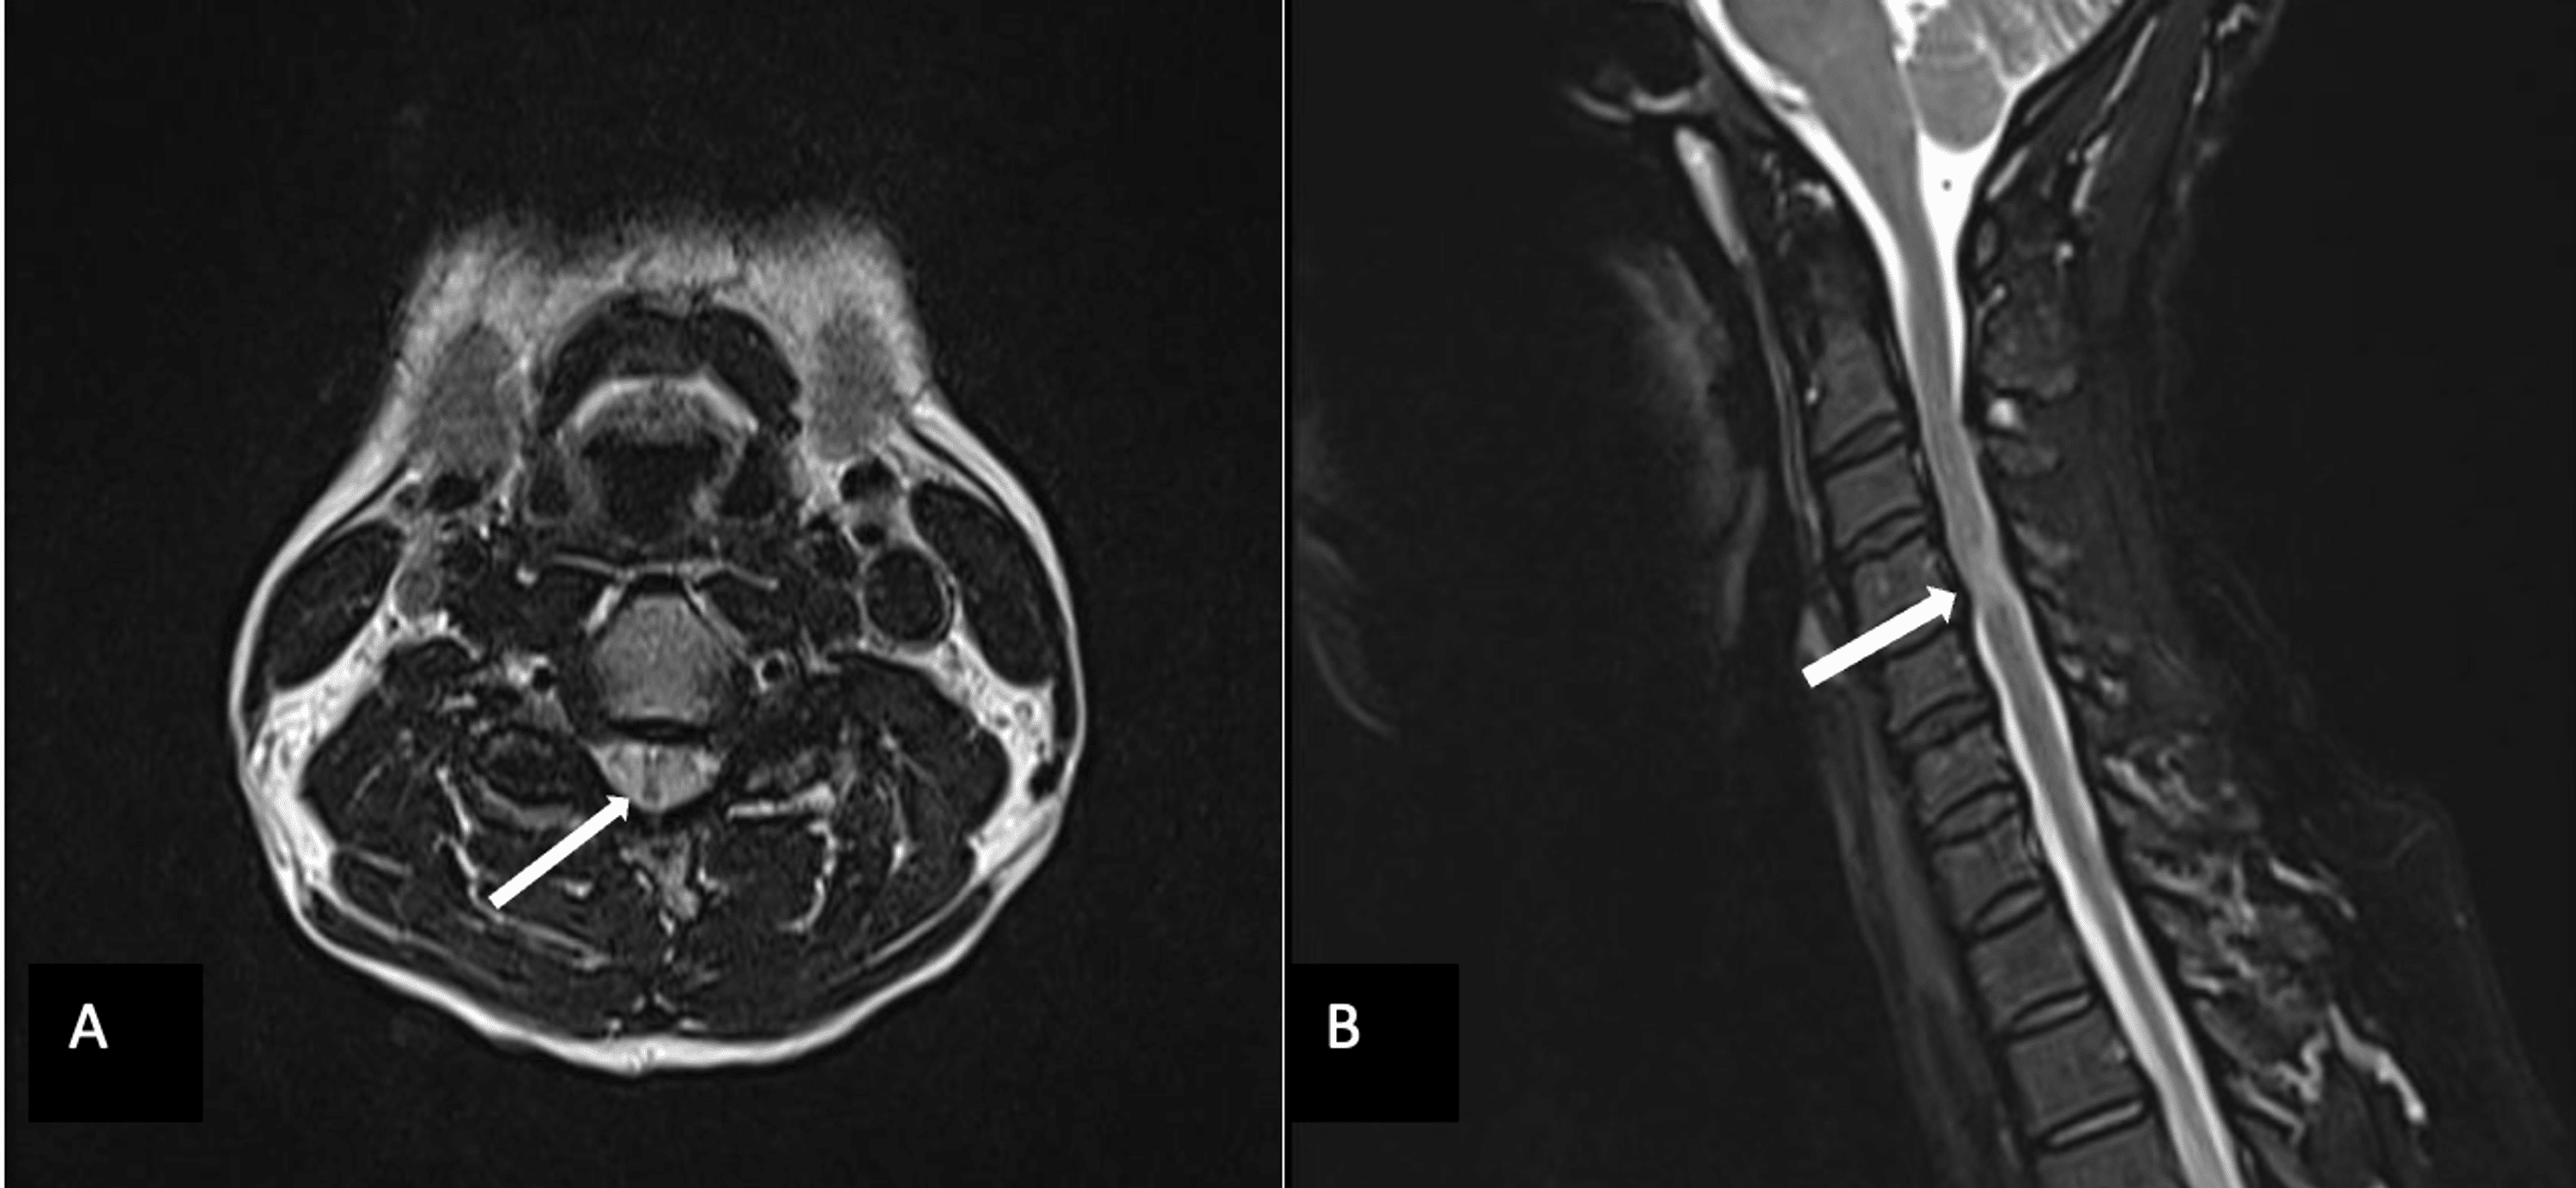

Cureus Management of Craniocervical Instability in Spondyloepiphyseal Flexion Extension Mri Near Me Flexion and extension mri allows the physician to see the patient’s neck not only while it is in a supine position but also while. This type of diagnostic imaging. The cervical spine flexion and extension views demonstrate the seven vertebrae of the cervical spine when the patient is in a. Extended mri (mean 32.9°) and prone ctm (mean 32.6°) are. Flexion Extension Mri Near Me.

Cervical Spine MRI in extended (a, b) and flexed (c, d) position. The Flexion Extension Mri Near Me The authors suggest that the usefulness of obtaining additional flexion and extension mri sagittal views reveals greater functional cervical cord impingement in. Extended mri (mean 32.9°) and prone ctm (mean 32.6°) are both performed in a very similar position to prone myelographic images (mean. The purpose of the study was to determine the value and utility of flexion and extension. Flexion Extension Mri Near Me.